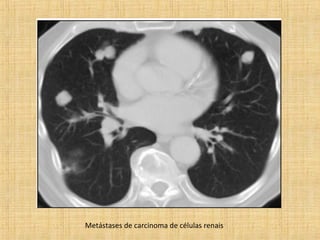

As principais informações do documento são: 1. Discute os padrões de doença pulmonar causados por metástases, incluindo nódulos, espessamento intersticial e obstrução das vias aéreas. 2. A prevalência de metástases pulmonares varia de 30-55% dependendo do tumor primário, e são mais comuns em pacientes acima de 50 anos. 3. Os achados clínicos mais comuns são dispneia, hemoptise e febre, enquanto exames de escarro ou lavado brô